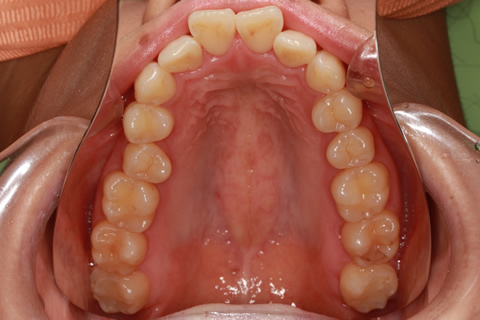

治療前

治療中(開始直後)

治療中(開始半年後)

治療後

- 年齢・性別

- 25歳女性

- 治療期間

- 2年0ヶ月

- 抜歯

- 上下4番抜歯

- 治療費

- 110万円

- 治療内容

- 施術の副作用(リスク)

- 表側矯正と比較して、力学的な操作性が複雑なため、ボーイングエフェクトを起こしやすい。